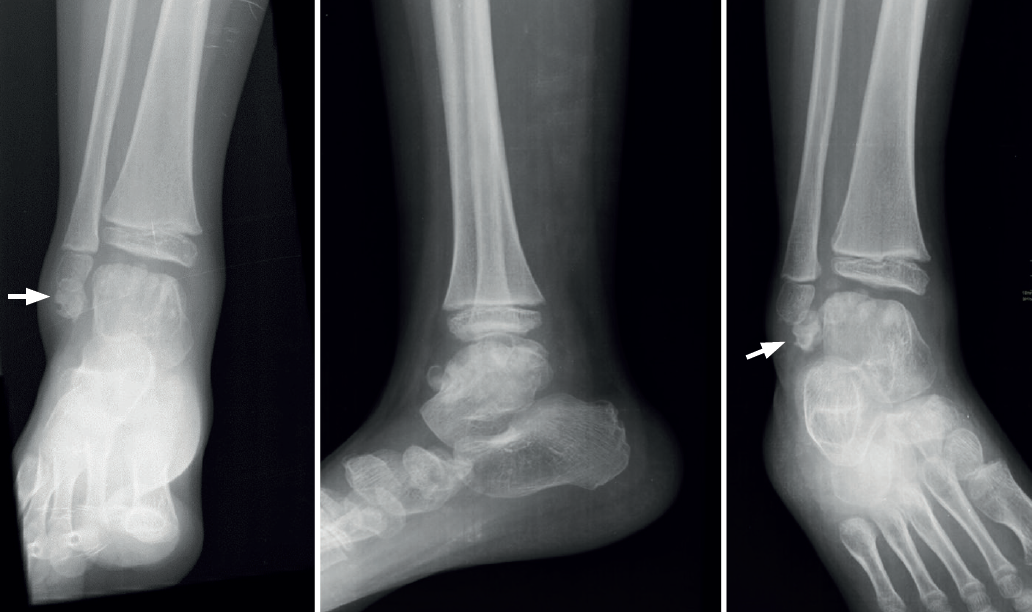

El síndrome de Trevor o displasia epifisaria hemimélica es acaso la forma más característica de alteración del desarrollo del astrágalo. Toda la bibliografía coincide en su rareza, al describir casos aislados casi siempre en edad infantil(44,45) y algunos con afectación generalizada de las epífisis de una mitad del cuerpo(46,47), cifran en 150 los casos comunicados hasta 2018 y se replantean este dato por la confusión diagnóstica que puede darse, ya que, en el caso del astrágalo, la apariencia radiológica puede ser muy variable(48) o incluso cuestionable al ser bilateral, como el caso de una mujer adulta de 42 años con pie plano doloroso publicado por Dávila y Llanos en nuestra revista(49).

En adultos (Figuras 6 y 7), se cita como causa de pinzamiento doloroso en la cámara posterior del tobillo(50), aunque también como causa de impingement anterior(51), o confundirse con un osteocondroma a pesar de sus diferencias histológicas. Mientras el osteocondroma reproduce una arquitectura similar a la de la placa de crecimiento, la displasia epifisaria hemimélica muestra en su cubierta cartilaginosa áreas con acúmulos de condrocitos y pequeñas áreas de cartílago calcificado no reabsorbido(52). Por otra parte, la presencia de osteocondromas en la parte posterior del astrágalo es muy rara. En una serie de 7 casos en los que se produjo rotura a través del pedículo en relación con ejercicio físico, Carpintero et al. no señalan ninguna en esta localización(53).

Algunos autores lo han relacionado también con una infección neonatal(56). El aspecto radiológico puede aparentar una fractura y así relacionarse con microtraumatismos repetidos en la infancia o inestabilidad(57), aunque su principal característica es la articulación del fragmento posterior con el calcáneo , llegando a formar una prolongación en consola (Figura 8).

En su evolución suele presentar dolor, grados variables de afectación articular y edema óseo visible en los estudios por RM(10) que lleva a plantear tratamientos quirúrgicos en la serie de 4 casos de Rammelt et al.(58).